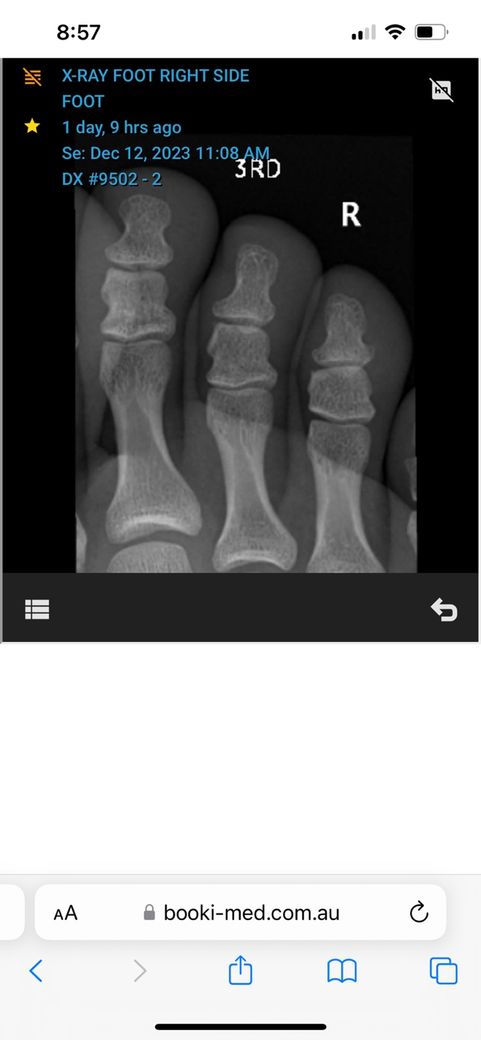

• 1번 째 사진

• 3번 째 사진

• 올리신 엑스레이 사진을 통해서 보았을 때에는 뼈의 골절 등 이상 소견이 보이지 않습니다. 다만 인대나 근육 등 부위에 대해서는 평가가 제한됩니다. 아무래도 추측건대 발레를 시작하고 발 부위에 충격이 반복되다 보니 충격으로 인한 조직 부종 및 염증 등이 생겼을 가능성이 높아 보입니다. 엑스레이 검사를 통해서는 보다 정밀한 소견들을 알 수 없습니다.